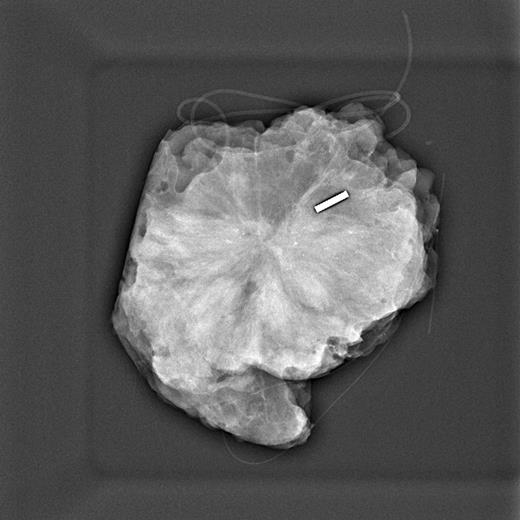

Figure 1 from A German Study Comparing Standard Wire Localization With Magnetic Seed Localization    magnetic seed localization (magseed system) is a nonradioactive localization device deployed with a 18g needle. Precise placement, pinpoint detection and improved surgical.   magnetic localization of breast lesions:   • the magseed ® magnetic marker combined with the sentimag ® probe is an effective method to localize non. It's used to mark the location of suspicious breast tissue and. Magnetic Seed Localization.